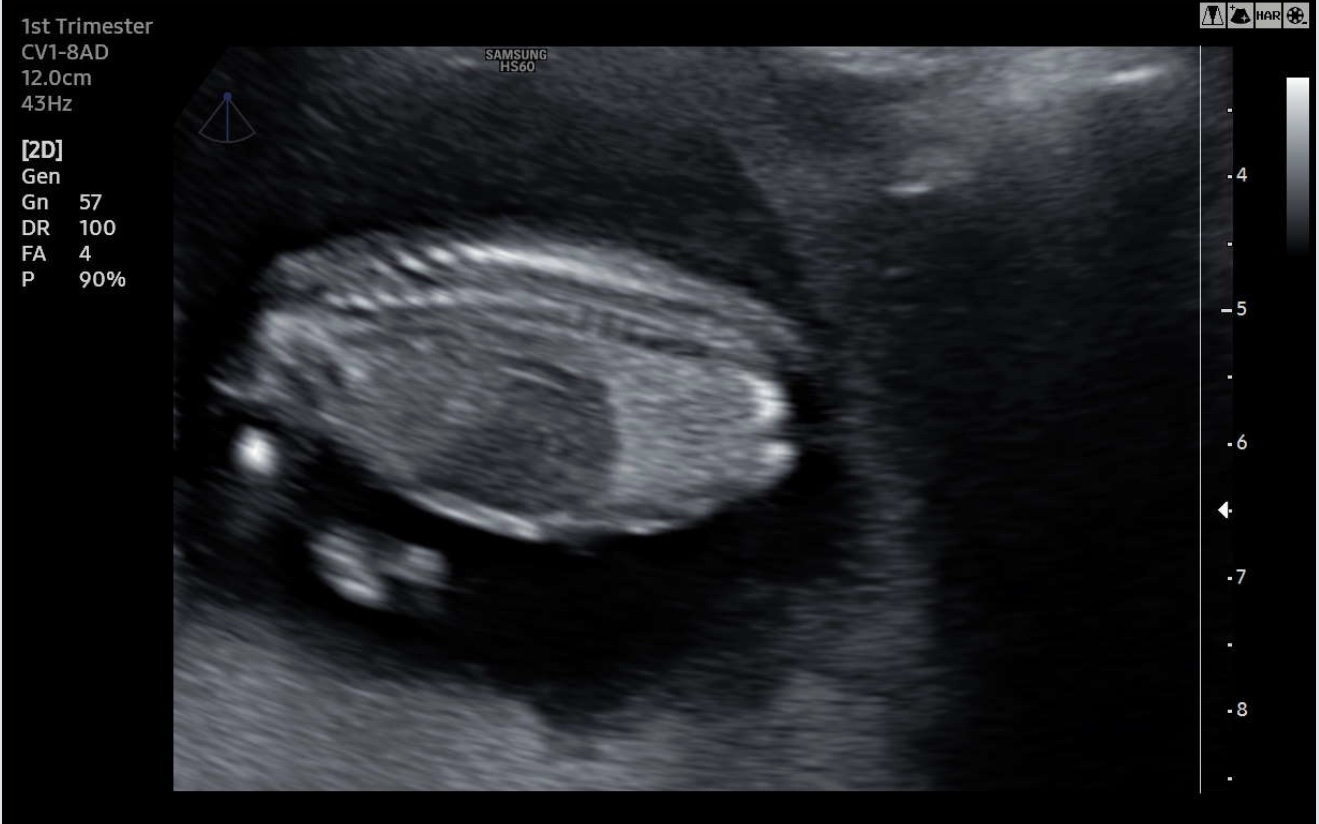

I have found more pictures that are maybe useful. Unfortunately no clear picture from the side with a nub what makes me think boy. Please help me with your guesses:-)Attachment 43795Attachment 43796Attachment 43797Attachment 43798Attachment 43799Attachment 43800Attachment 43801Attachment 43802

Also found this image of a possible potty shot. Any boy or girl parts visible over here?